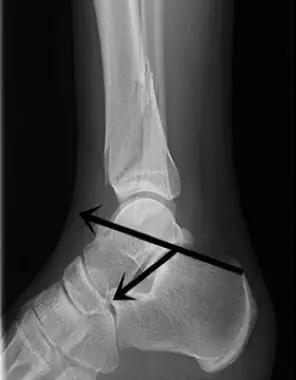

踝关节

- 结节关节角:是在跟骨后关节面最高点与跟骨结节间做一连线,再在跟骨前端背侧最高点与后关节面最高点做另一连线,连线相交成角,称为结节关节(Böhler角)。

- 正常值:25°~40°

- 临床意义:跟骨结节关节角减小,提示跟骨骨折或扁平足;跟骨结节关节角增大,提示弓形足。

- Gissane角:从跟骰关节面连线与后关节面后缘连线 的夹角。

- 正常值为:120°~145°。

- 临床意义:跟骨骨折时角度可能会发生变化,该角度提示前中后关节的关系。